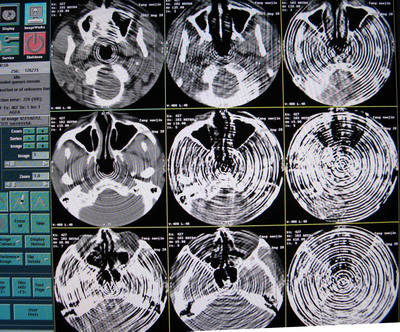

6.原因會不會是數據到了 OC 這邊重建出了問題呢,用原來正常圖像的原始數據用相同的條件進行重建,發現正常圖像的原始數據重建出來的圖像出現了偽影,如下圖:

正常的圖像

重建出來的偽影圖像

7.用原來掃出來不正常空氣圖像的原始數據用相同條件反復重建如下圖:

從上面幾幅圖可以看出,每次重建出來圖像出現偽影的地方都不同,原來不正常的圖像可以重建出正常的圖像,再次證明了原始數據是沒有問題的。